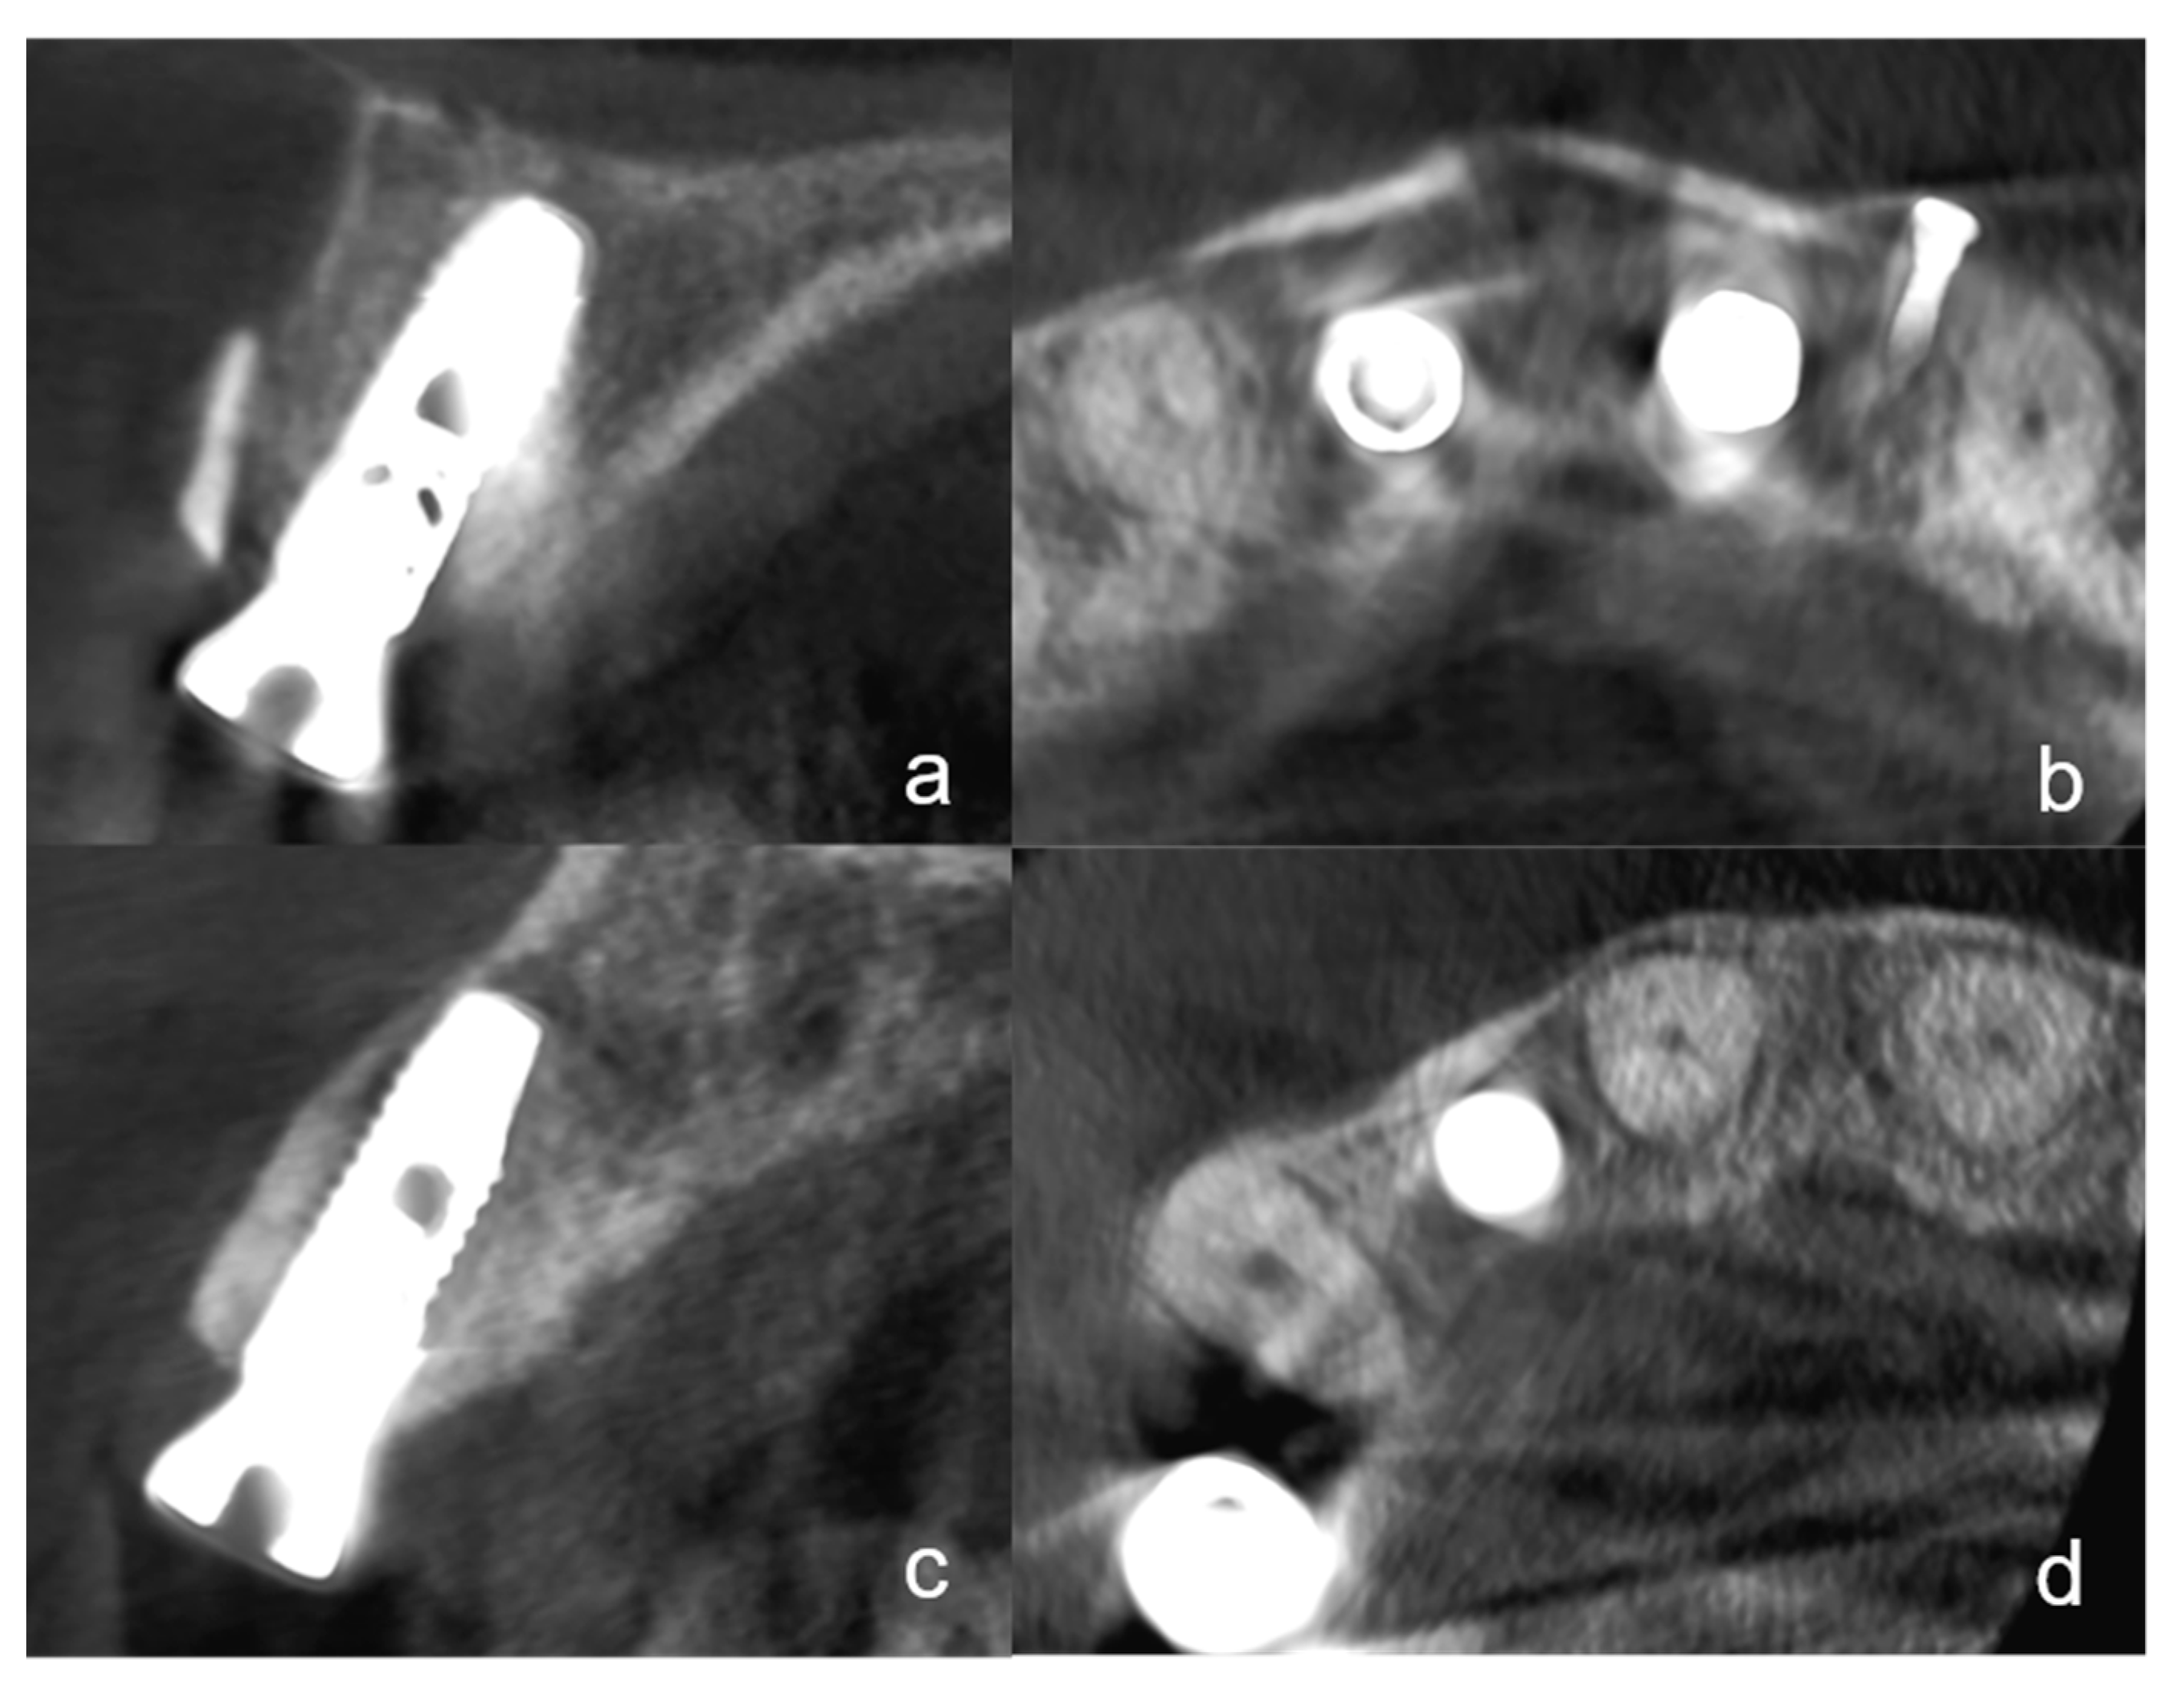

At the time of implant exposure (3 months after augmentation), a CBCT was made to assess the osseointegration, the buccal lamella, and the horizontal hard tissue loss. All implants were placed at the hard tissue level and the implant surfaces were completely covered by native bone or hard tissue graft (autogenous dentin or bone). To evaluate the horizontal bone loss the CBCTs at the time of implant exposure were analyzed. The hard tissue loss was assessed considering mesial and distal aspects. Only the highest value at the mesial or distal margin was included in the analyses. Additionally, the integrity of the buccal lamella was assessed using the CBCT (Figure 4a–d). Possible hard tissue loss with exposed buccal implant surfaces was noted.

Figure 4.

(a): A cone-beam computed tomography (CBCT) in the sagittal plane shows an implant regio 11 with the tooth-shell technique (TST) at the time of the implant exposure. The integrity of the buccal lamella is visible. The dentin shell does not appear to show any resorption. (b): The same CBCT in the axial plane with the implant in region 11 and another implant region 21. Two buccal dentin shells are clearly visible. (c): This figure shows a CBCT in the sagittal plane of an implant region 12 with BST at the time of implant exposure. At this plane, the complete integrity of the buccal lamella can be seen. The bone shell is no longer visible and appears to have undergone replacement resorption. (d): The same implant in the CBCT in the axial plane. No bone shell can be seen.

3.2. Radiographic Evaluation

At the time of the follow-up, 3 months after augmentation with simultaneous implantation evaluation of the CBCTs showed two cases with horizontal hard tissue loss at the mesial or distal implant shoulder. One case with TST exhibited a hard tissue loss of 1 mm and one case with BST of 0.5 mm. There were no significant differences between the two groups at all three statistical levels. The integrity of the buccal lamella was preserved in all implants (Figure 4a,d). All implants were completely covered with hard tissue (no more than 1 mm loss).

In all cases with TST, the dentin shell was clearly visible. In some cases with BST, the bone shell was not visible in the CBCT or had a partial replacement resorption.

The tooth-shell technique described in this study is a variation of this technique using autogenous dentin instead of bone, which avoids bone harvesting procedures from retromolar mandibula or other donor sites. Recent research has shown that autogenous dentin shares many similarities with bone in its structural and chemical compositions and is, therefore, suitable as a bone substitution material with comparable biological properties and less resorption of the graft [17,18]. Autogenous dentin, however, has been shown to be involved in the remodeling process of bone and to be successively replaced by newly formed bone through replacement resorption more homogenously than bone grafts but leaving some remnants of the tooth material [16]. Partial demineralization of the dentin, which was performed by a 10% EDTA solution in this study, is able to promote the replacement resorption and new bone formation due to the exposure of the collagen network and the release of osteogenic growth factors—e.g., bone morphogenetic proteins. Completely demineralized dentin, on the other hand, is resorbed faster than new bone can be formed due to enzymatic degradation of the collagen network [28]. The clear visibility of the tooth shell in the CBCT image and the bone shell that is partially demarcable suggest a lower resorption rate for the TST than for the BST.

The radiographic at re-entry after 3 months showed a decent horizontal bone loss in only a few cases. The integrity of the buccal lamella was demonstrated in the CBCT for all implants. The peri-implant probing depths as well as the radiological results and the adequate ISQ values suggest osseointegration. Another limitation of the study is that a CBCT was only performed at the time of implant exposure. Therefore, the extent of resorption of the augmentation cannot be assessed in the observation period. In the case of the TST, however, a dentin shell was visible in the CBCT in all cases, while in BST the bone shell was not visible in some cases or apparently had a partial replacement resorption. Comparable studies show that the resorption of autogenous dentin is lower than that of bone [18].